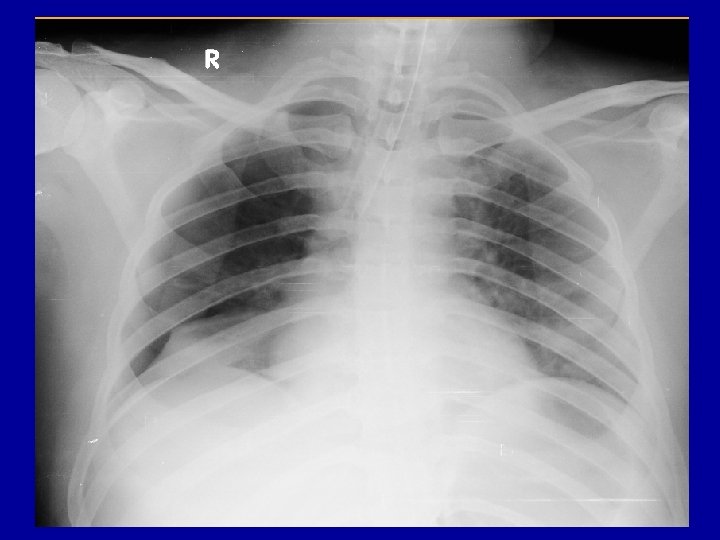

Diagnose-5 places to look for • • • External Long bones Chest – x ray chest Abdomen - FAST Pelvis and Retro peritoneum Shock in a multiply injured patient is “hemorrhagic shock” unless proved otherwise

Radiology • X rays – – Chest – Pelvis – C Spine – lateral view • FAST • CT ? ? Do Not Shift Hemodynamically unstable patient to Radiology Room